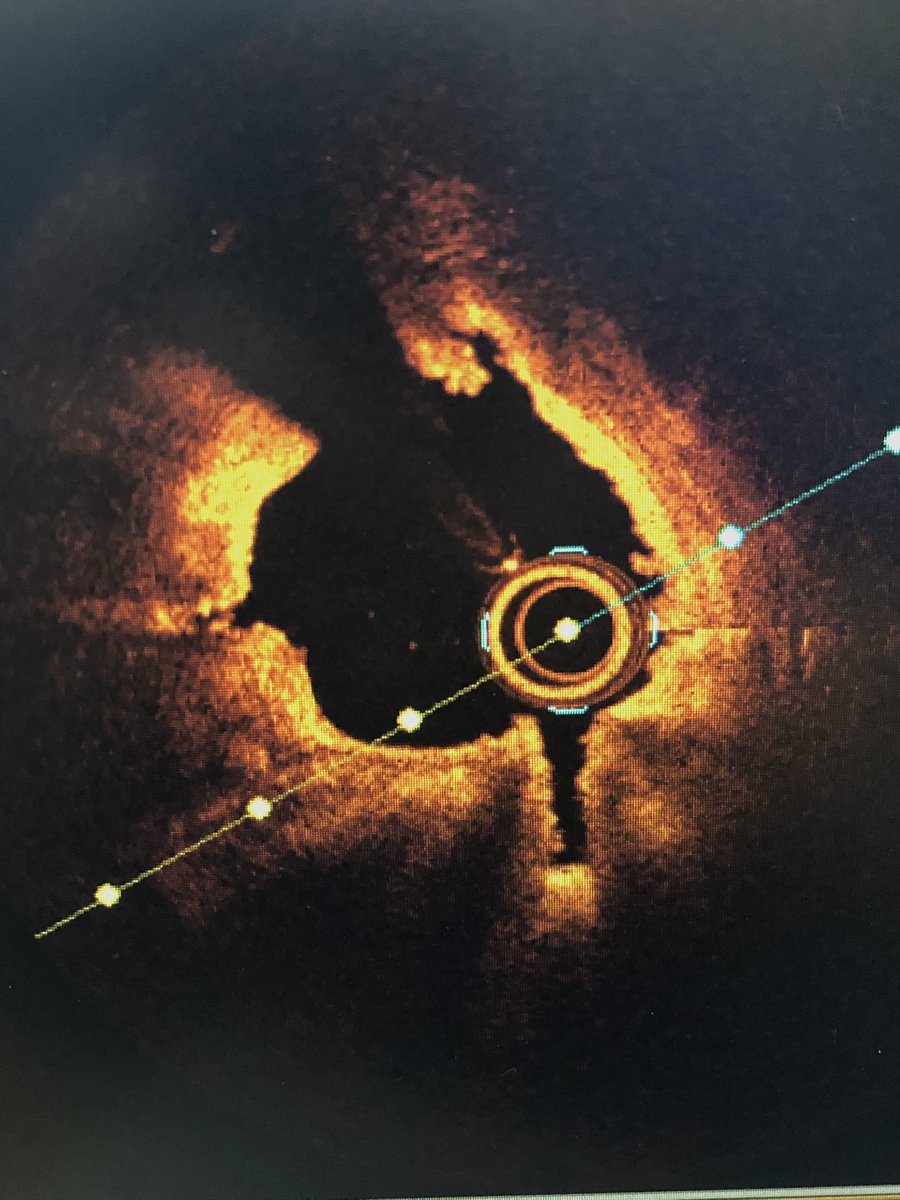

Richard Sohn MD@RSohnMD·

1/ WHY “very late” stent thrombosis? ➡️ #OCT can show you! 👀 CASE: 63M w/ old RCA stent, now w/ sudden severe CP EKG & initial angiography 👇🏼👇🏼

OCT run after dilation w/ 2.0 mm balloon to allow better imaging